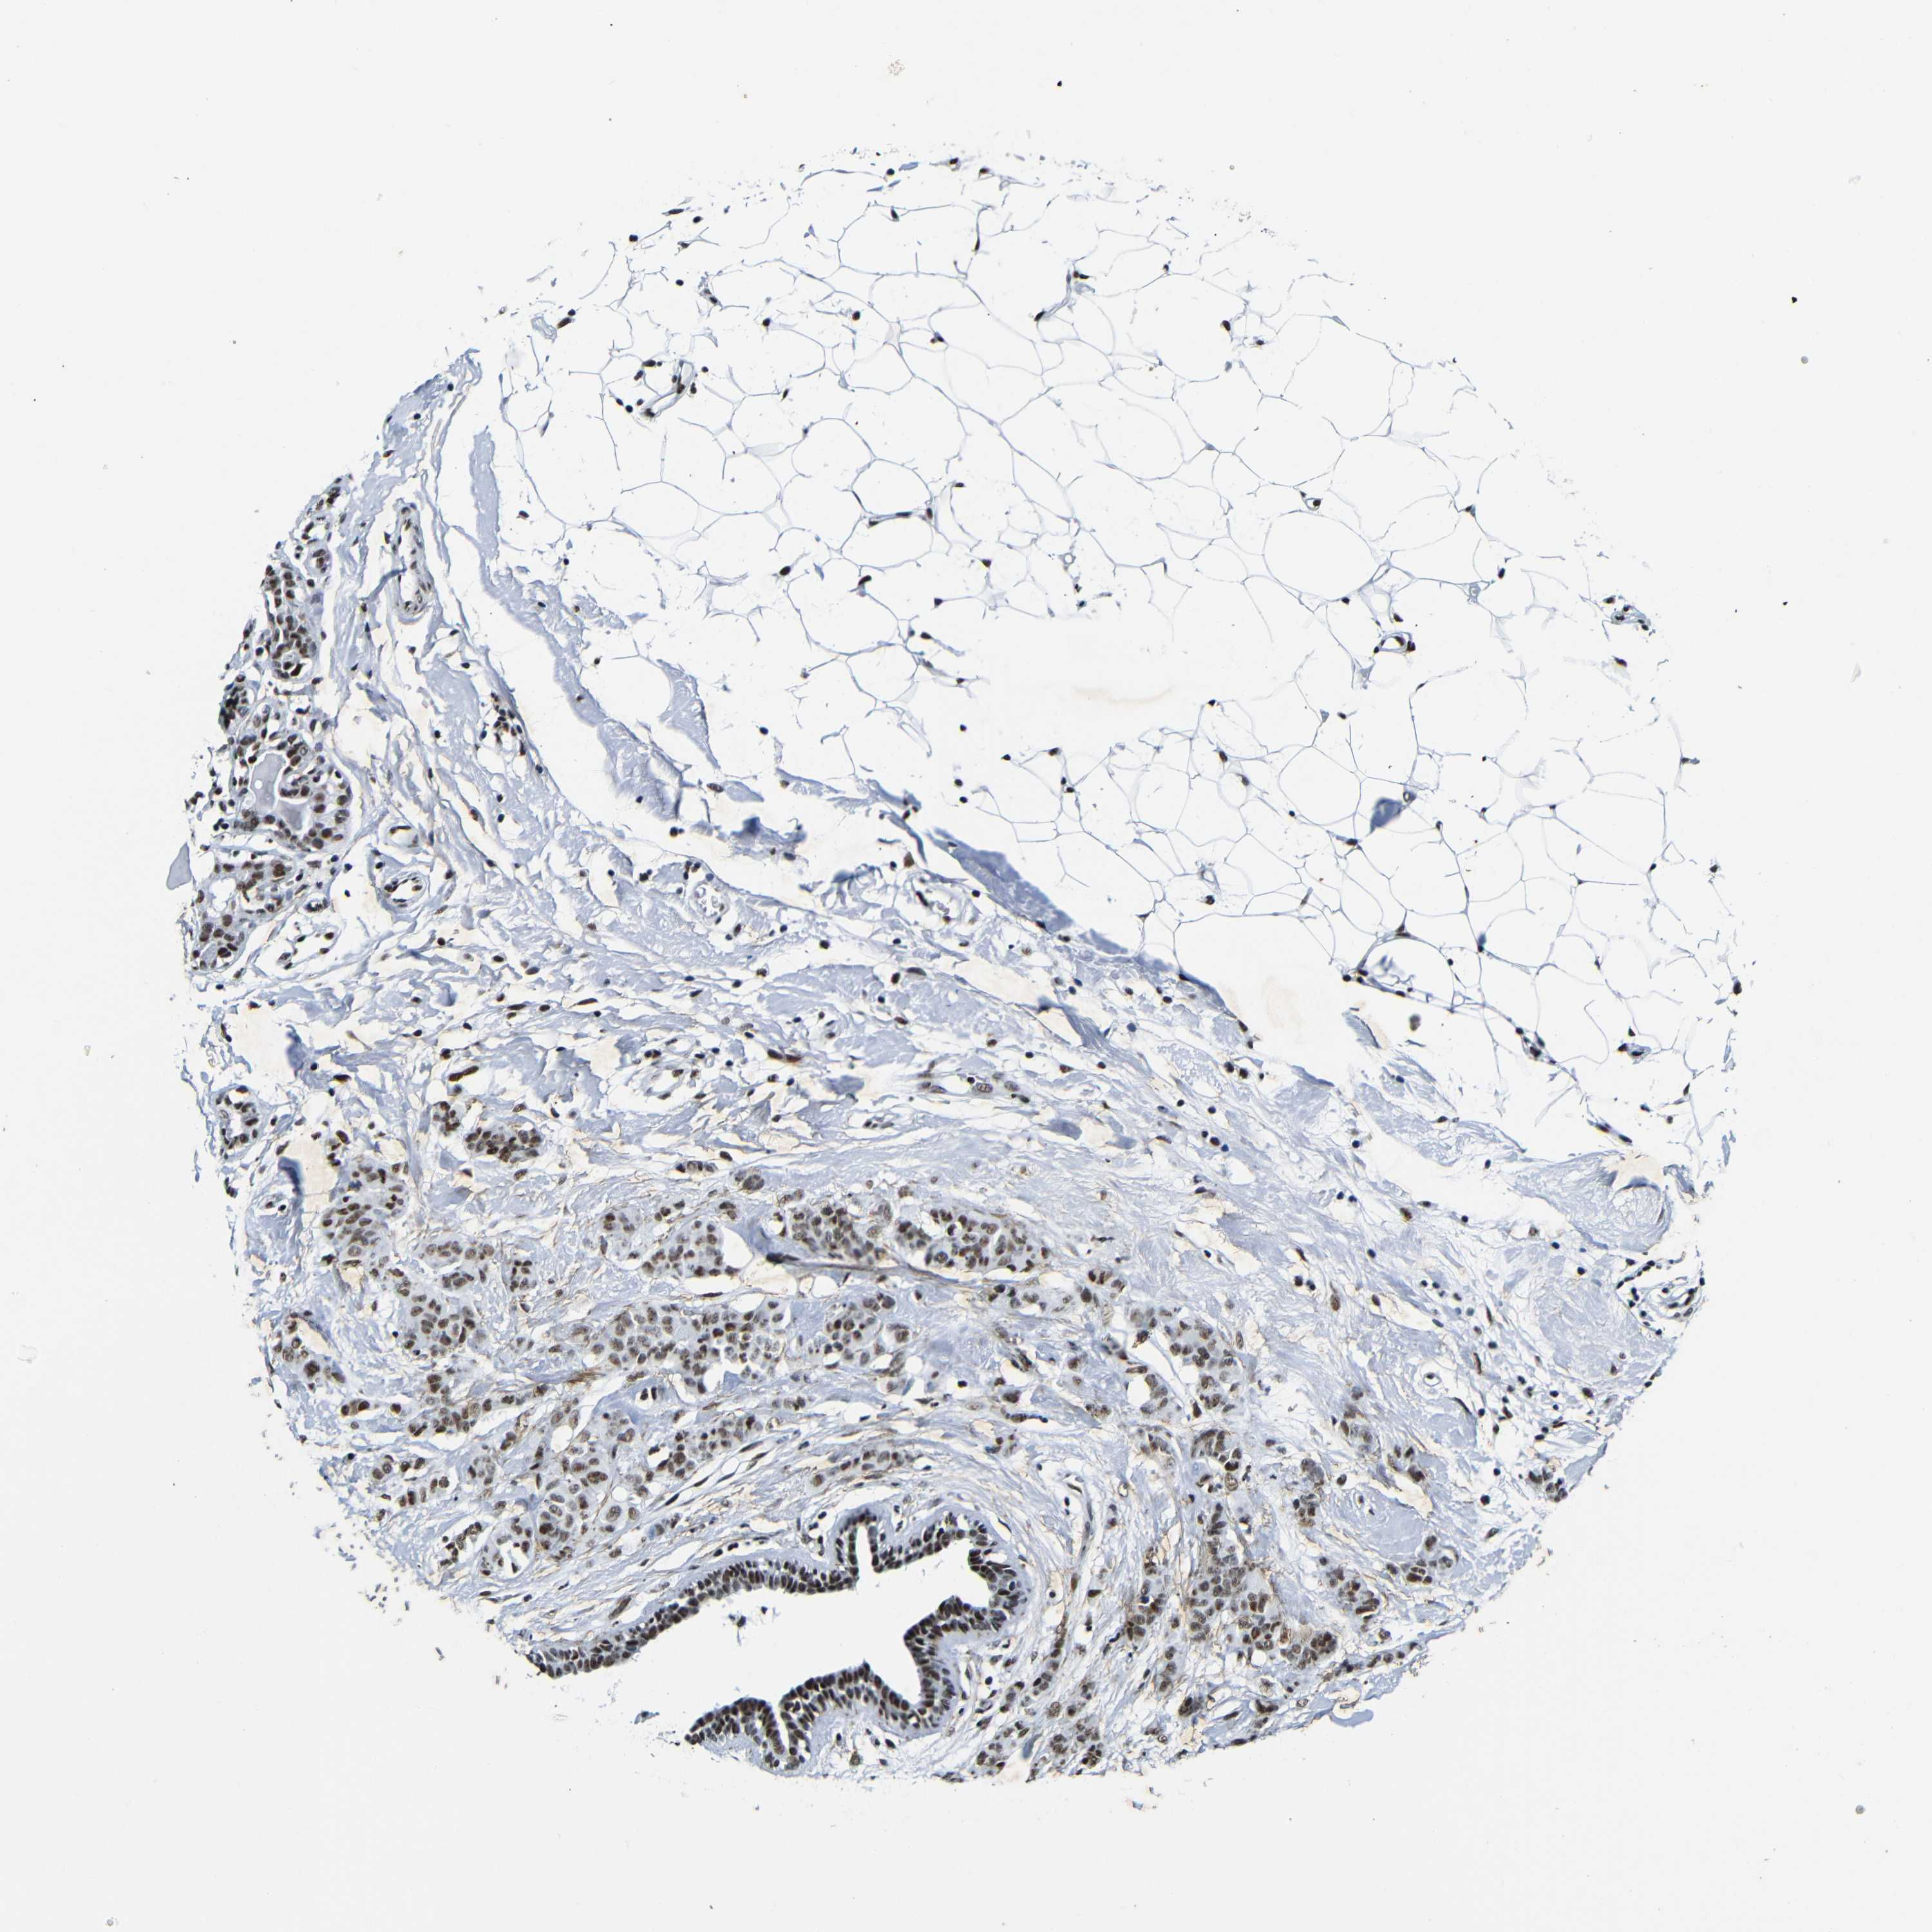

BRCA TCGA BRCA VALIDATION PROTEIN EXPRESSION